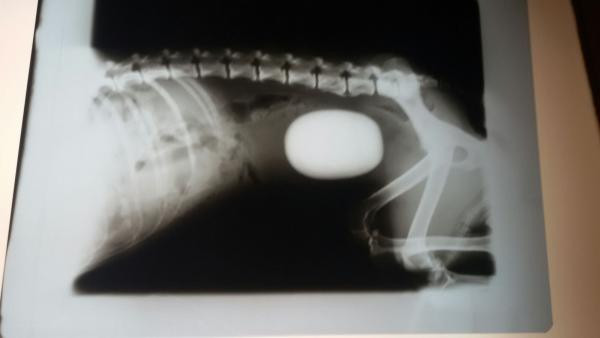

Eureka é unha cadeliña a que os seus donos non trataban demasiado ben. Tiña un cálculo renal de canto rodado do tamaño dun ovo e que a simple vista parecía un tumor. Por sorte cedéronola e puidemos darlle a atención veterinaria que precisaba. Foi operada con éxito e agora merece atopar unha familia de verdade que a mime e coide como merece.